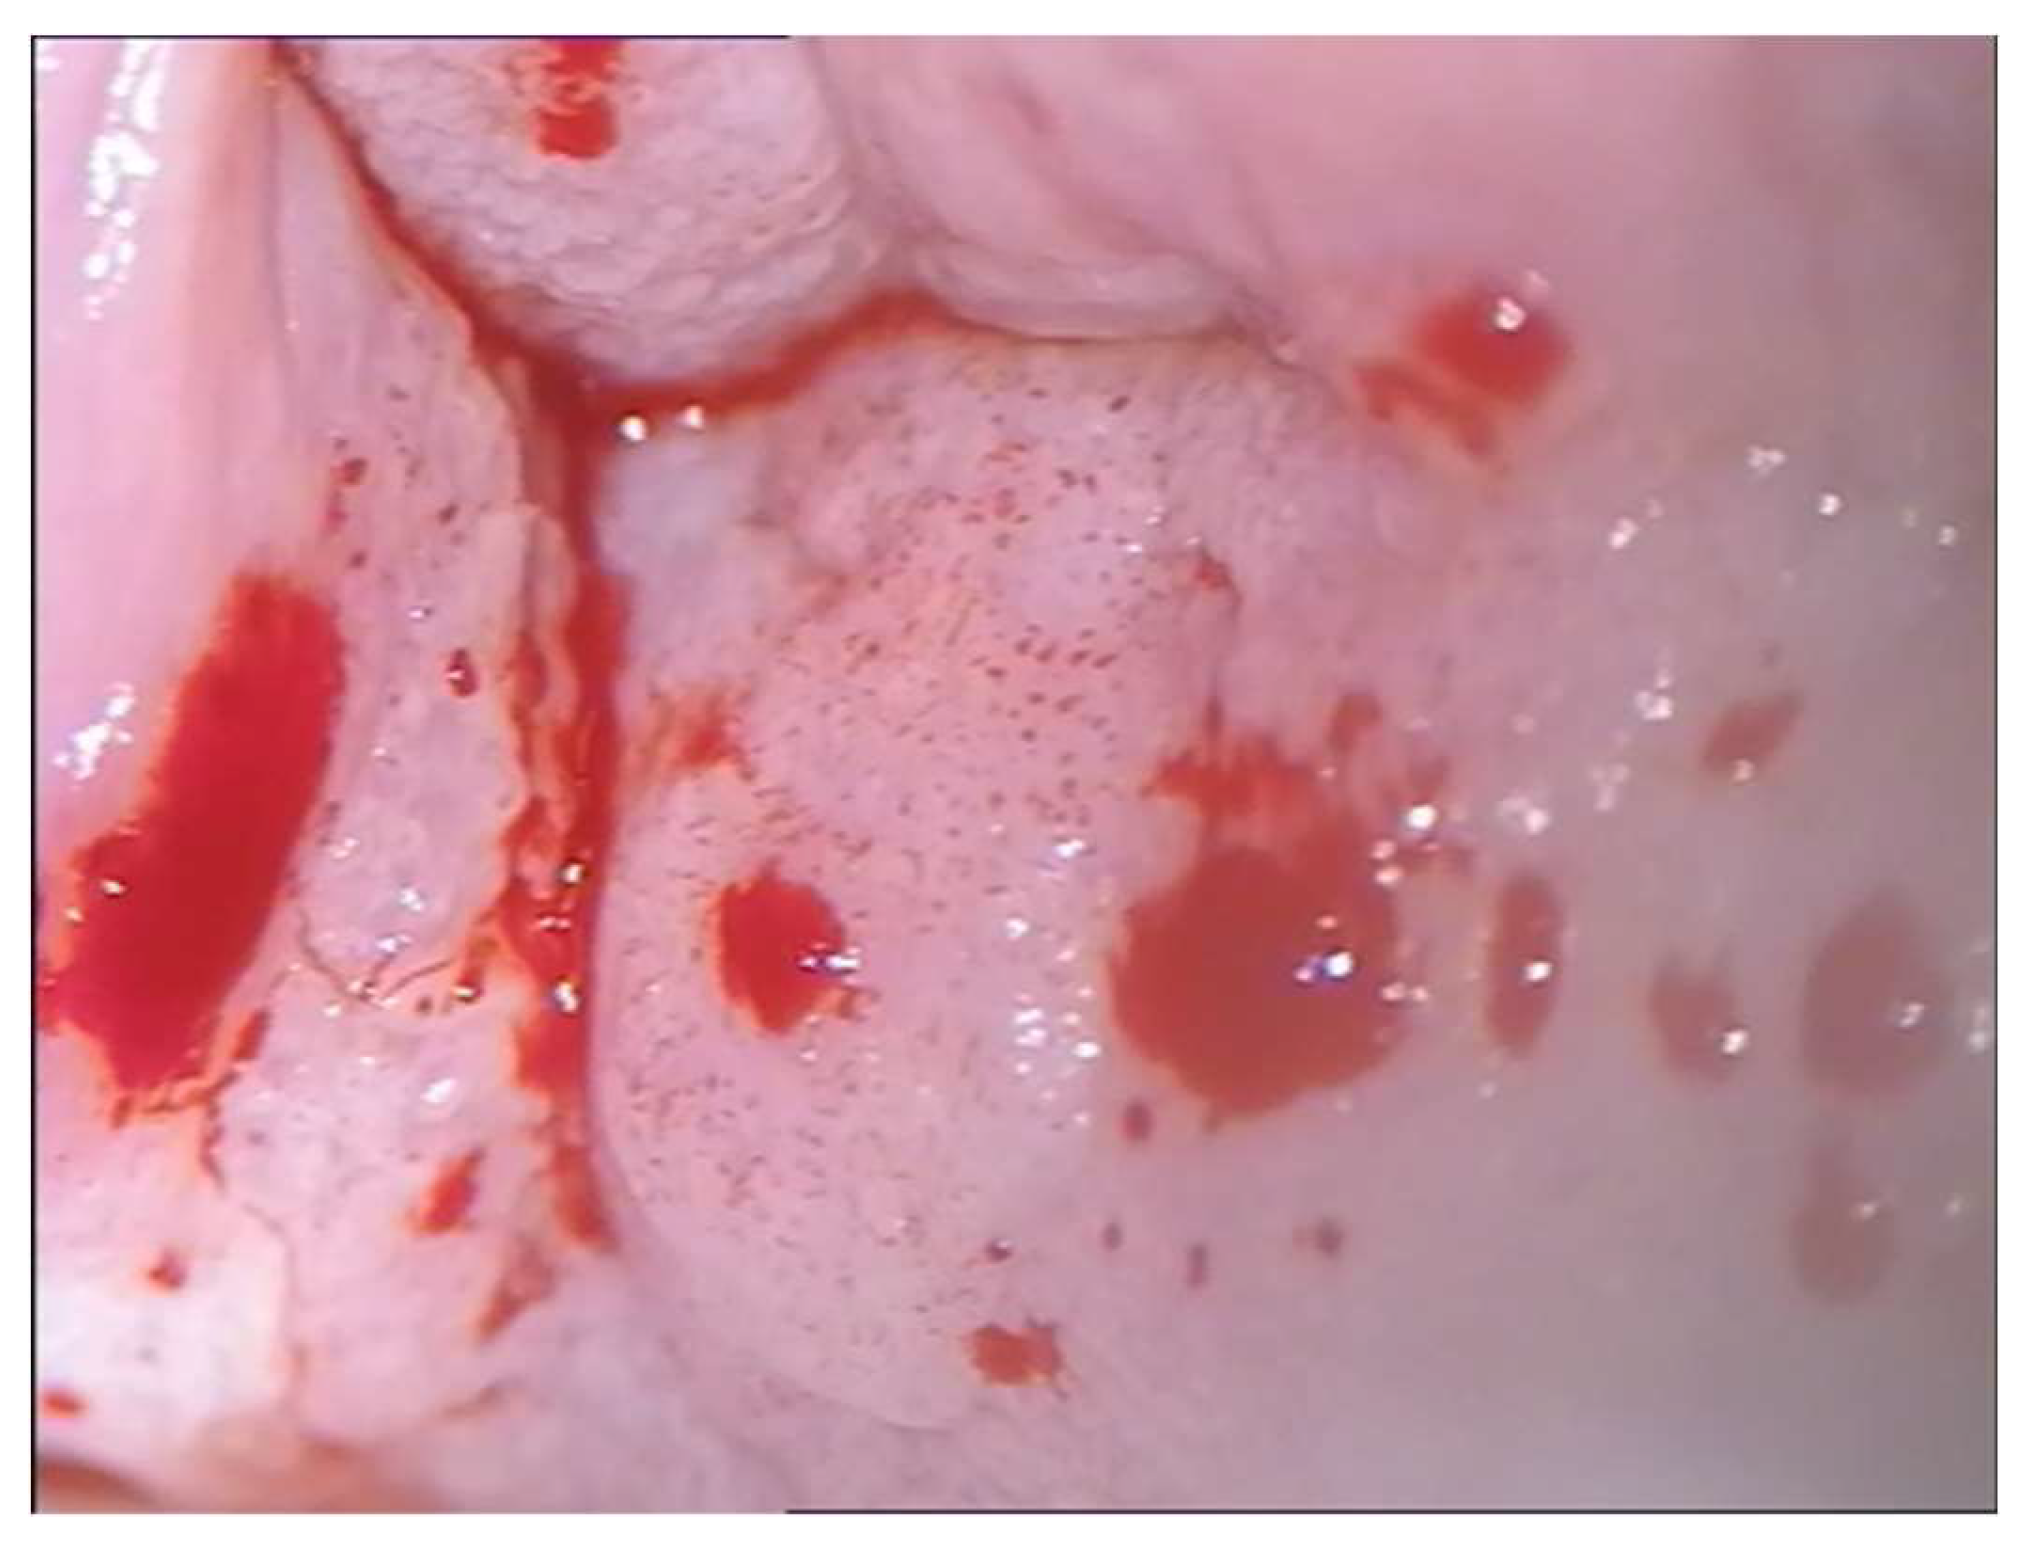

- Cong, Qing MD; Fu, Zhongpeng MD; Zhang, Di MD; Sui, Long MD Importance of colposcopy impression in the early diagnosis of posthysterectomy vaginal Cancer. J Low Genit Tract Dis, 2019,23,1:13-.

| Vaginal Carcinoma | 62 16 | multipapillary easily bleeding | vaginal dome and posterior wall | Radioterapy | ||